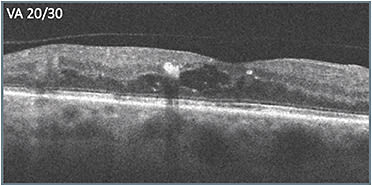

A 54-year-old female presented after having been treated by another physician with approximately 8 treatments for nonproliferative diabetic retinopathy (NPDR) and reduced vision (20/40). Leakage was present on the previously obtained initial ultra-widefield angiography. The previously obtained initial OCT scans (A) showed cystic fluid but intact retinal layer integrity, with the exception of some attenuation of the outer retinal layers, and only 1 noticeable hyperreflective focus nasally. Edema persisted and therapy was switched. After 2 treatments with the second therapy, vision improved slightly to 20/30 and edema improved (B).